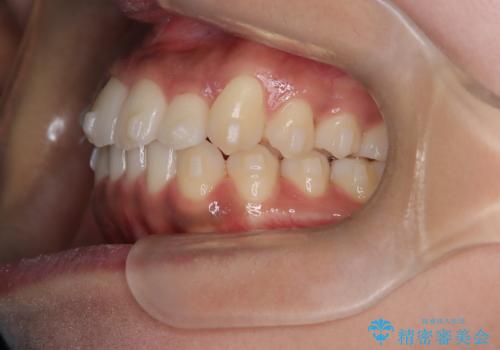

【インビザライン】笑ったときに目立つ八重歯をなおしたい

- 笑ったときに八重歯が見えることを主訴に来院されました。

下の前歯が一本足りない患者様でしたので、シミュレーションを作り、事前に患者様と治療ゴールのイメージをしっかり共有したうえでインビザラインを用いて治療を行っています。

奥歯を後ろのほうに動かすことで、前歯も少し下がることができ、矯正後の口元も満足していただきました。